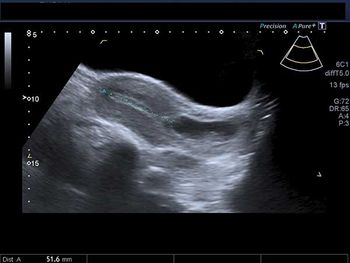

A 40-year-old woman reports a 20-week history of amenorrhea. What is your diagnosis based on these images?